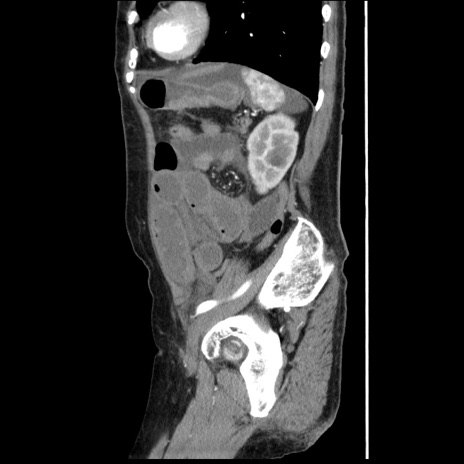

症例1(矢状断像)

【症例】80歳代女性

【主訴】腹痛

【現病歴】8時間前から腹痛あり来院。

【既往歴】糖尿病、脂質異常症、子宮体癌にて子宮全摘術

【身体所見】意識清明・会話良好だが腹痛で苦悶様、全腹部にわたって反跳痛と圧痛あり

【データ】WBC 13600、CRP 0.14、LDH 224、CK 90